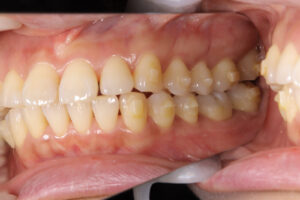

Invisalign failed

奥歯が噛んでいない

Invisalign correction failure

orthodontic treatment